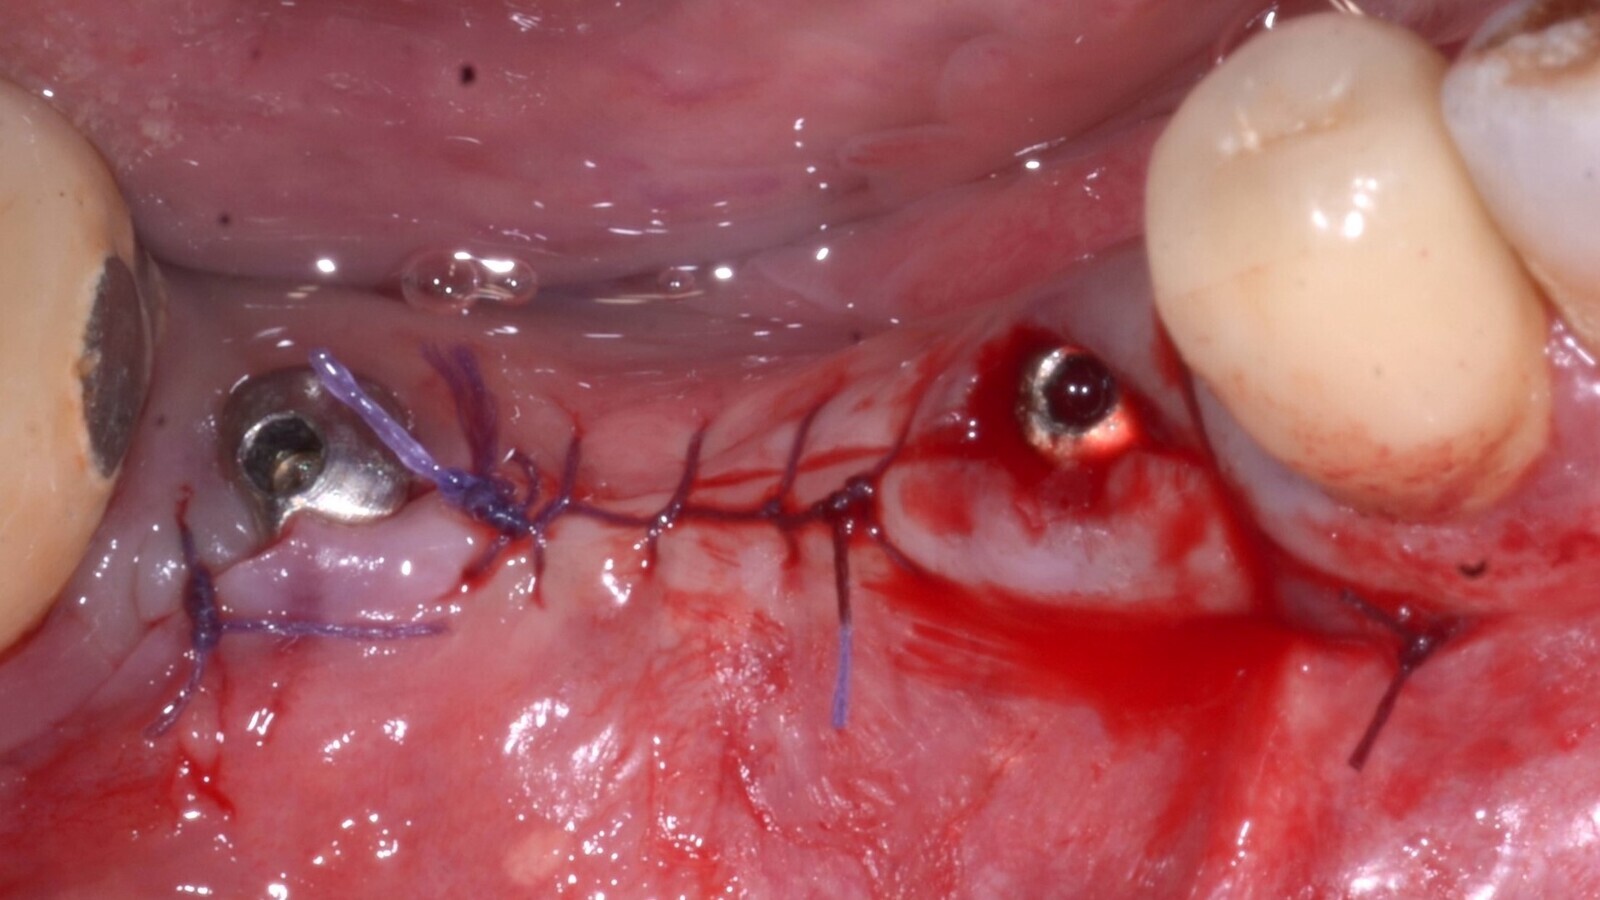

Los colgajos se cerraron con suturas Vycril 5-0 para favorecer la cicatrización de primera intención (Figs.7 y 8).

Fig. 7. Pasivación del colgajo para permitir el cierre de primera intención. Obsérvese la inserción de la tercera clavija estabilizadora de la lámina cortical flexible.

Fig. 8. Cierre del colgajo y cicatrización por primera intención.